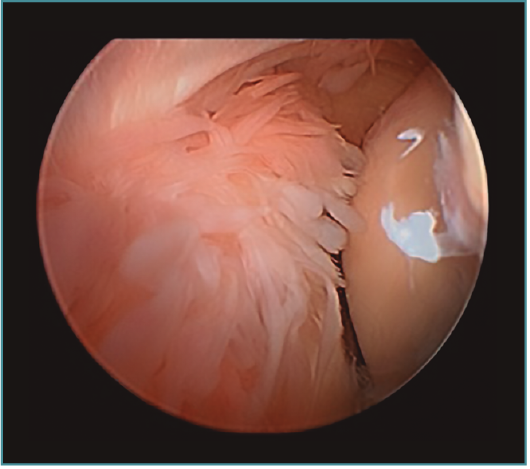

Cirugía artroscópica

La artroplastia osteocapsular artroscópica persigue los mismos objetivos que la cirugía abierta, con una serie de ventajas como son la menor incisión, la menor agresión para las partes blandas, la disminución del sangrado intraoperatorio y la mayor precisión en el fresado y recontorneado óseo, al contar con la magnificación proporcionada por la óptica, así como el mejor control del dolor del paciente en el postoperatorio y el comienzo precoz de la rehabilitación. Sin embargo, es un procedimiento demandante técnicamente que exige tener una amplia experiencia previa con procedimientos más simples. Los factores que aumentan la complejidad del procedimiento con respecto a otro tipo de artroscopias del codo son, dejando aparte los relacionados con la causa que desencadenó la rigidez, que ya fueron mencionados: el volumen articular reducido, la escasa distensibilidad de la cápsula engrosada y la presencia de cicatrices intraarticulares e hipertrofia sinovial, que dificultan de manera importante la visualización y el trabajo articular que tenemos que hacer. Esto, sumado a la restricción de 2 horas de isquemia como máximo de las que disponemos, puede poner en jaque a cirujanos inexpertos que tengan que terminar el procedimiento sin haber conseguido concluir los objetivos del tratamiento (Figura 7).

Figura 7. Sinovitis exuberante que no deja ver la articulación radiocapitelar desde el portal anteromedial proximal, en una artritis postraumática con volumen articular reducido.